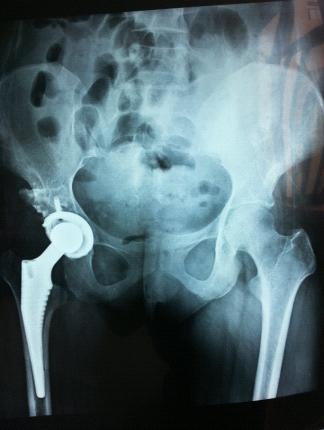

術(shù)前平片 術(shù)后平片

討論:髖關(guān)節(jié)結(jié)核好發(fā)于中青年,男性多于女性,髖關(guān)節(jié)結(jié)核除了體內(nèi)原發(fā)病灶通過(guò)血或淋巴等途經(jīng)感染髖關(guān)節(jié)外,尚可因髖臼外方的髂骨結(jié)核大轉(zhuǎn)子結(jié)核,后方骶髂關(guān)節(jié)結(jié)核等蔓延至髖關(guān)節(jié),此外脊柱結(jié)核亦可通過(guò)腰大肌膿腫流注至髂恥束而引發(fā)髖關(guān)節(jié)結(jié)核。髖關(guān)節(jié)結(jié)核通常發(fā)病緩慢,全身中毒癥狀不顯著,疼痛是髖關(guān)節(jié)結(jié)核最先出現(xiàn)的癥狀,初時(shí)疼痛多不甚明顯,休息后及可減輕,少數(shù)急驟發(fā)病的髖關(guān)節(jié)結(jié)核可有劇烈疼痛和關(guān)節(jié)活動(dòng)受限,大多數(shù)病人早期癥狀不重,不重視,誤診、誤治,隨著病情的發(fā)展出現(xiàn)關(guān)節(jié)功能障礙,本患者4年前診斷“髖關(guān)節(jié)結(jié)核”,入院時(shí)跛行,股骨頭明顯骨質(zhì)破壞,經(jīng)規(guī)則結(jié)核化療3周后行手術(shù)治療,術(shù)后繼續(xù)規(guī)則結(jié)核化療18月,結(jié)核痊愈,但患者關(guān)節(jié)功能嚴(yán)重受影響,關(guān)節(jié)周圍肌肉攣縮,導(dǎo)致患肢上移,縮短,股骨頭缺失,股骨頸殘端上移異位融合,假關(guān)節(jié)形成,術(shù)前采用3D技術(shù)將患髖關(guān)節(jié)按1:1比例實(shí)體打印復(fù)制呈型,術(shù)中充分松解髖關(guān)節(jié)周圍肌肉,用小號(hào)人工假體置入并松解關(guān)節(jié)周圍攣縮肌肉組織,將人工關(guān)節(jié)復(fù)位檢查髖關(guān)節(jié)各方向活動(dòng)無(wú)阻礙,術(shù)后患者雙下肢基本等長(zhǎng),步態(tài)正常,手術(shù)取得滿意效果。